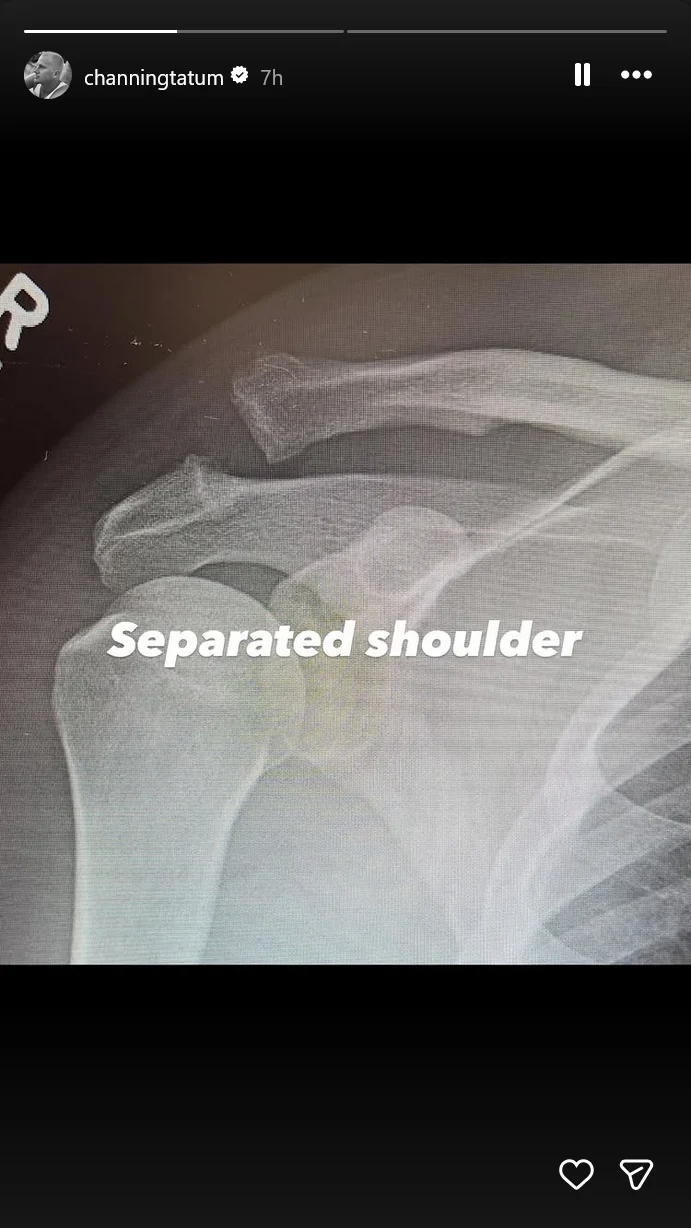

On his Instagram Story, the 45-year-old actor gave fans a more technical look at the damage, posting “before and after” X-rays of the injury. The “after” shot prominently featured a surgical screw holding his shoulder joint in place, which Tatum jokingly captioned, Screwed shoulder.